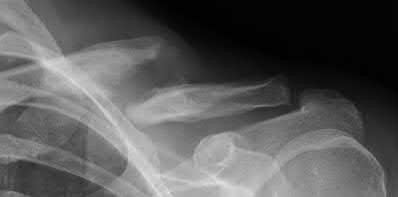

Question 5:

A 45-year-old male is involved in a high-speed motor vehicle collision and presents with the cervical spine radiograph findings typical of traumatic spondylolisthesis of the axis. Which of the following describes the primary mechanism of injury for this specific fracture pattern (Hangman's fracture)?

Correct Answer: Hyperextension and axial loading

Explanation:

A 'Hangman's fracture' is a traumatic spondylolisthesis of the axis (C2) involving fractures through the pars interarticularis. The classical mechanism of injury in modern trauma (e.g., unrestrained passenger hitting the windshield) is hyperextension and axial loading. Flexion-distraction typically causes Chance fractures, while flexion-compression typically causes anterior wedge or teardrop fractures.